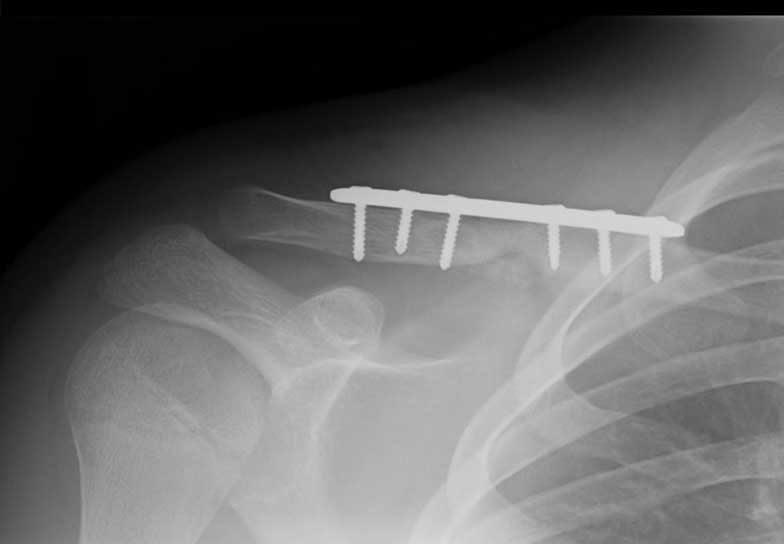

This man is 38 years old and originally fractured his clavicle when much younger. It was left to heal naturally but unfortunately healed in a poor position. He fell while playing soccer and fractured through the previous mal-union and callus. He had surgery and within just six weeks was almost healed and had a good range of motion, function and strength.

Malunion fracture before surgery

Malunion fracture after surgery

Move the slider to compare before surgery and 6 weeks after surgery